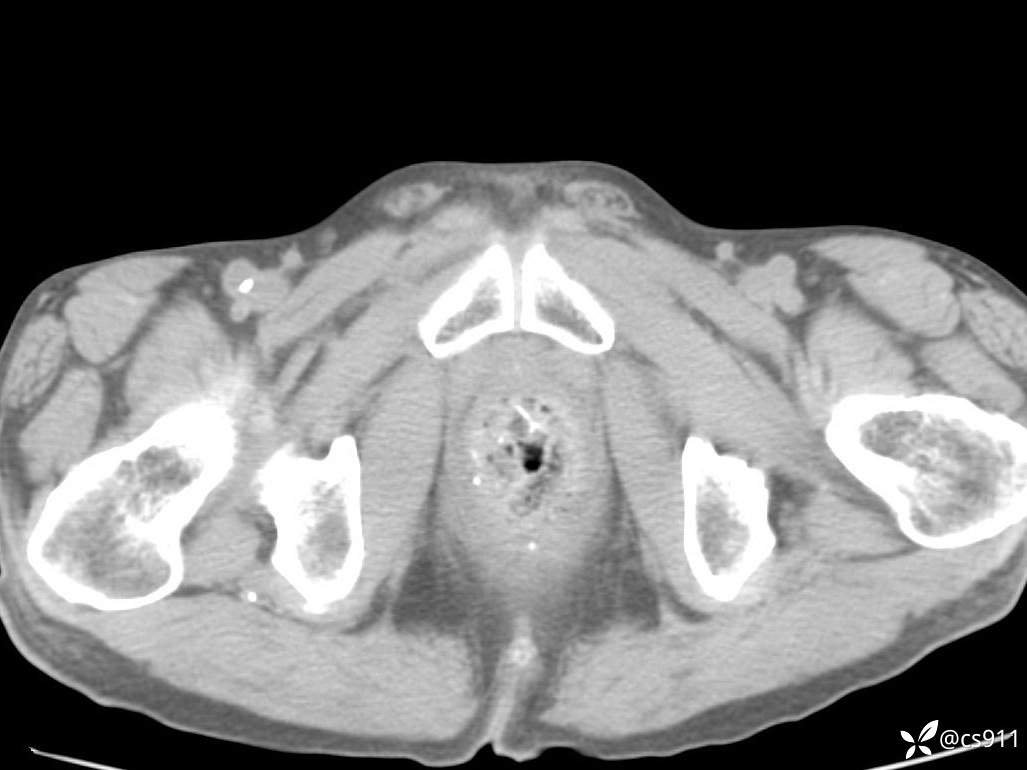

急腹症之急诊CT,原因?答案公布

男,77岁,腹痛、腹胀伴恶心呕吐1天。呕吐胃内容物,非喷射性呕吐,有咖啡色样胃内容物,诉有胃穿孔病史。查体:全腹平,下腹部压痛,全腹无反跳痛,叩诊呈浊音,移动性浊音阴性,肠鸣音减弱,1-2次/分。肛检:直肠未扪及明显肿物,可触及大量粪块。

血淀粉酶(AMY) HH 1859 U/L 35-135